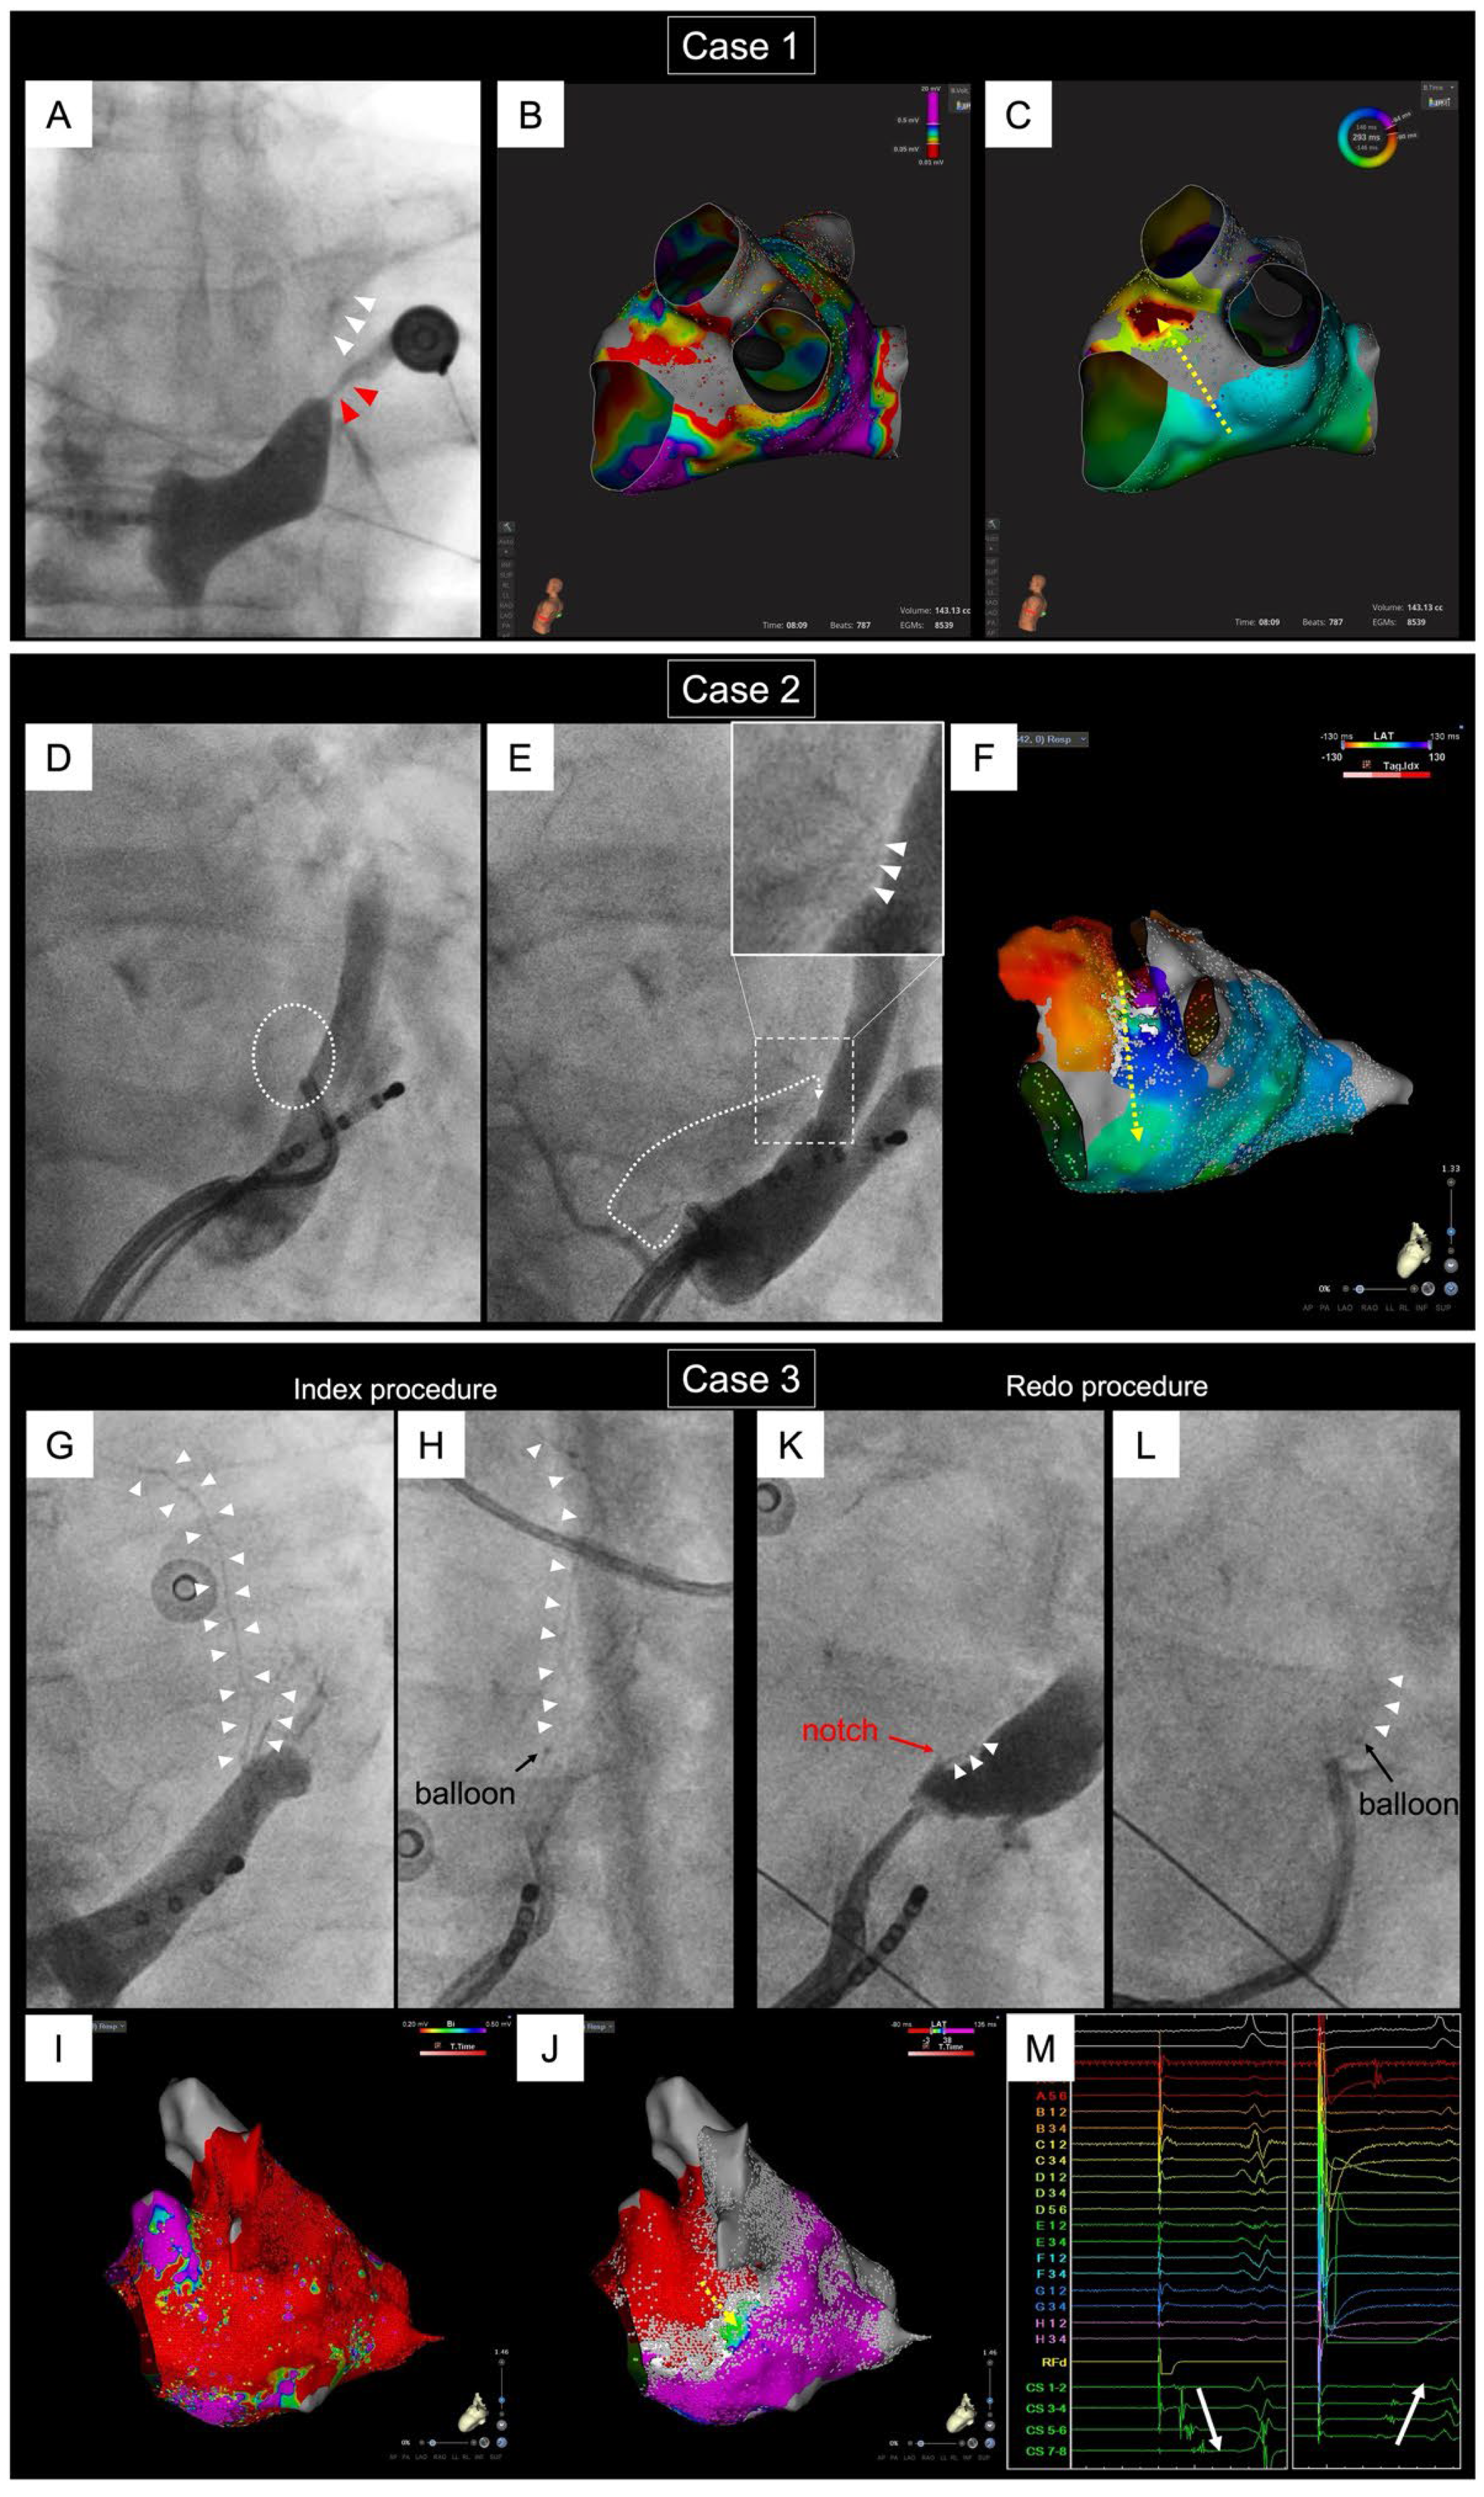

- Yokoyama, M.; Yamashita, S.; Yoshimura, M.; Yamane, T. A case of pseudo-endocardial gap during mitral flutter: Pitfalls of the auto-annotation algorithm on the ultra-high-resolution mapping system. HeartRhythm Case Rep. 2023, 9, 126–128. [Google Scholar] [CrossRef] [PubMed]

- Vlachos, K.; Denis, A.; Takigawa, M.; Kitamura, T.; Martin, C.A.; Frontera, A.; Martin, R.; Bazoukis, G.; Bourier, F.; Cheniti, G.; et al. The role of Marshall bundle epicardial connections in atrial tachycardias after atrial fibrillation ablation. Heart Rhythm. 2019, 16, 1341–1347. [Google Scholar] [CrossRef]

- Takagi, T.; Derval, N.; Duchateau, J.; Chauvel, R.; Tixier, R.; Marchand, H.; Bouyer, B.; André, C.; Kamakura, T.; Krisai, P.; et al. Gaps after linear ablation of persistent atrial fibrillation (Marshall-PLAN): Clinical implication. Heart Rhythm. 2023, 20, 14–21. [Google Scholar] [CrossRef] [PubMed]